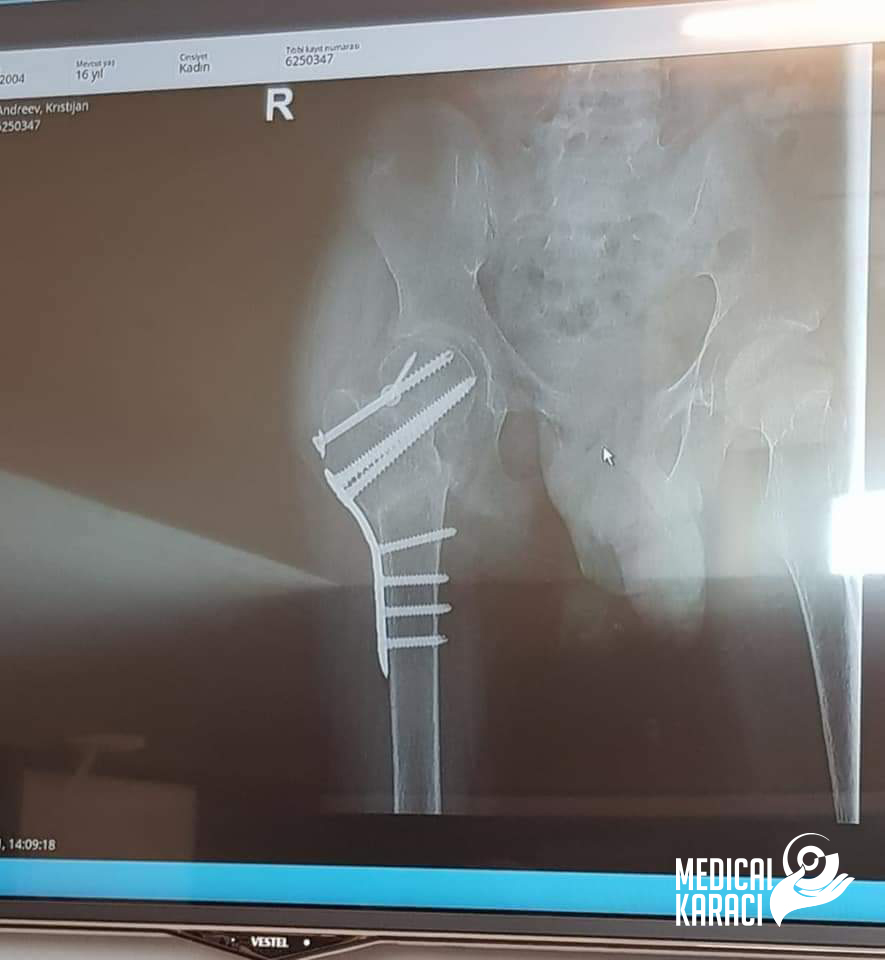

Kristijan is a child of 17 years of age who suffers from a very severe form of autism and epilepsy, in December 2020 he fell and was shot. Koga site in Macedonia kazuvaa ni deka nemoze da ho operiraat i deka nema nikogash veke da zastane na noge i da odi jas ne se otkazav, no nitu ti mila moja Zvezdelina Kara i Karaci Tours Medical denonokno istrazuvashe, him barashe i him najdobroto za Kristijan !! Kristijan blagodarenie na te te i na Prof. Dr. Mustafa Kürklü ZASTANA NA NOZE I ODI 🙏🙏Neznam kako da ti se zablagodaram za se shto napravi i pravish za Kristijan, za celata organizacija vo bolnicata Memorial Bahcelievler Hospital for the whole time that you are with us. That's why you rejoice and fight together with us🙏